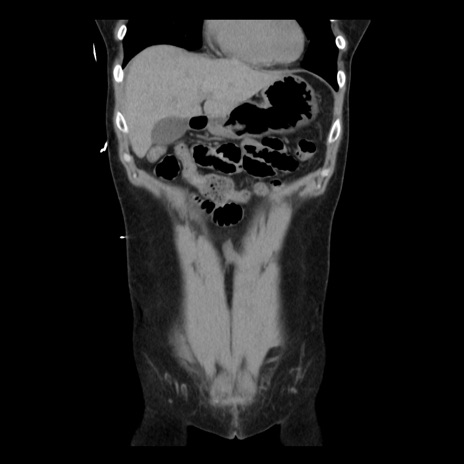

症例10(冠状断像)

【症例】 50歳代女性

【主訴】 腹痛

【現病歴】前日生レバーを食べた。今朝に排便あり。 昼前に突然発症の腹痛を生じ、当院救急外来を受診した。

【既往歴】 子宮筋腫にてで子宮全摘後

【身体所見】 意識清明、腹部:平坦、軟、下腹部やや左を中心に圧痛・反跳痛あり、筋性防御あり

【データ】WBC 7800、CRP 0.07